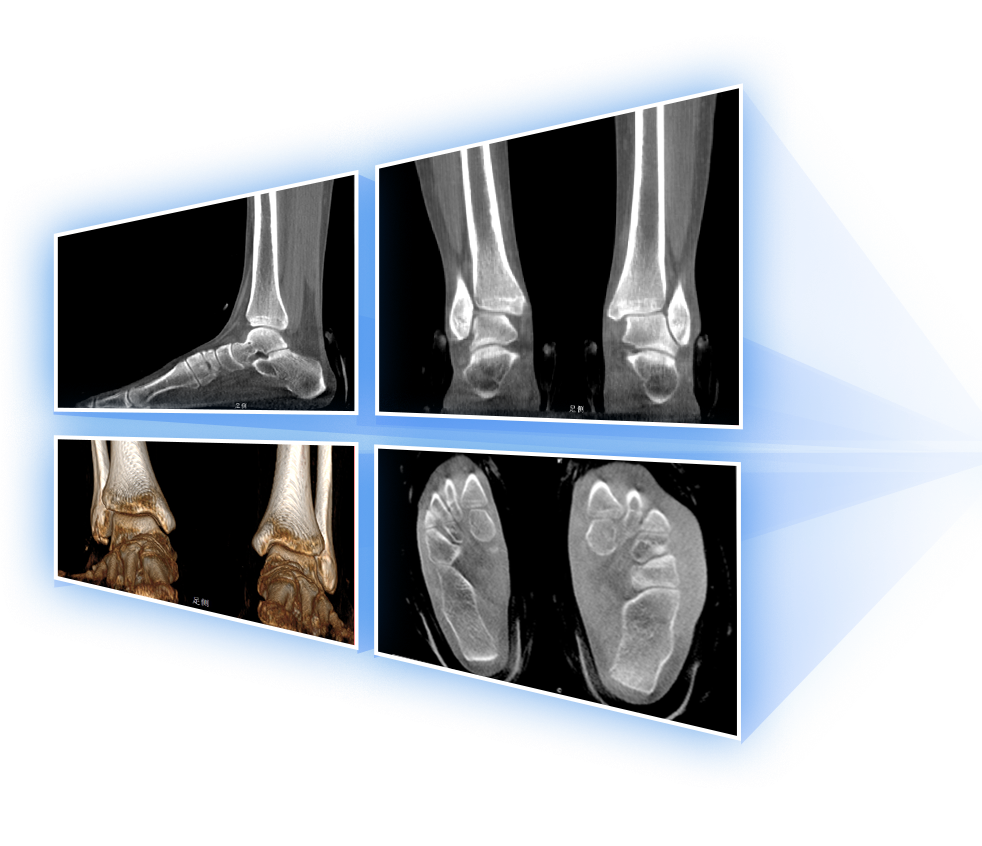

足踝

VR体绘制重建